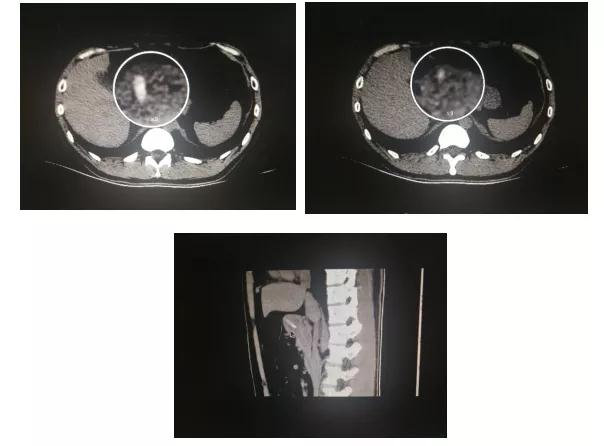

因考虑到枣核两端尖锐已引起消化道粘膜破裂穿孔,出血风险高,门诊以“胃内异物”收住入院。入院后患者诉上腹部剧烈疼痛,进食后加重,夜间多次痛醒史,伴呃逆嗳气,反酸烧心,食欲减退,大便色暗,质不成形。经请示脾胃一科鱼涛主任,予急查上腹部CT排除因异物引起的穿孔可能。为尽早解除患者病痛及规避穿孔出血风险,鱼涛主任安排行急诊胃镜下异物取出术。

胃内异物很少引起不适或只有轻微的上腹部隐痛胀满、恶心等症状。当异物阻塞于幽门时,病人常感觉上腹部疼痛、腹胀、呕吐。本例患者剧烈疼痛症状源于枣核两端尖锐同时侵入胃内粘膜深达肌层,CT影像结果可做证实。异物若不及时排出或取出,会损伤胃黏膜,造成胃溃疡、胃出血、胃穿孔、腹膜炎等疾病。